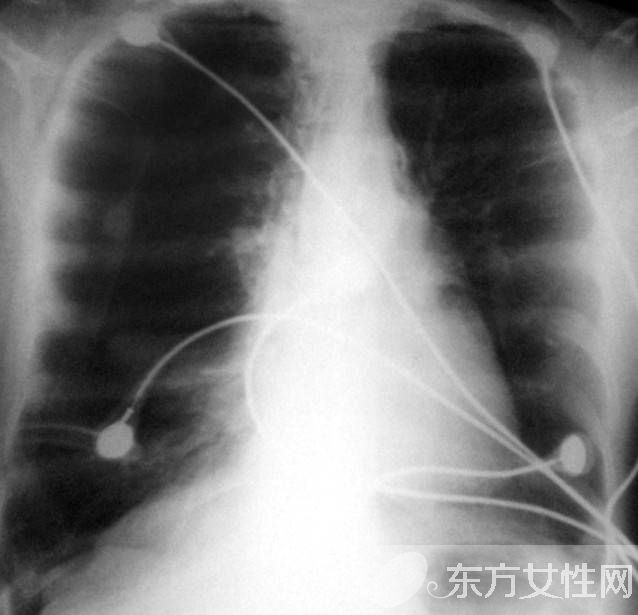

在正常的呼吸中,肺泡擴張后收縮,使氧氣進入血液,并且把二氧化碳排出?;忌戏螝饽[之后,肺泡失去彈性,為了代替,就過度擴張,以致破裂,因而減少了氧氣的攝入量。這樣一來,心臟及頸、胸、腹部與呼吸有關(guān)或控制呼吸的肌肉必須更加用力地工作,以便攝取足夠氧氣。此外,患者的兩肺膨大,從側(cè)面看上去有桶狀胸。肺氣腫病情進至嚴重階段,患者持續(xù)缺氧,同時過量的二氧化碳積聚在體內(nèi)。患者須要借助醫(yī)療措施來改善呼吸,包括使用機械輔助呼吸與面罩吸氧。最后,患者的呼吸功能可能完全衰竭。

發(fā)病緩慢,多有慢性咳嗽、咳痰史。早期癥狀不明顯,或在勞累時感覺呼吸困難,隨著病情發(fā)展,呼吸困難逐漸加重,以致難以勝任原來的工作。慢支在并發(fā)阻塞性肺氣腫時,在原有的咳嗽、咳痰等癥狀的基礎上出現(xiàn)逐漸加重的呼吸困難。當繼發(fā)感染時,出現(xiàn)胸悶、氣急,發(fā)紺,頭痛,嗜睡,神志恍惚等呼吸衰竭癥狀。肺氣腫加重時出現(xiàn)桶狀胸,呼吸運動減弱,呼氣延長,語顫音減弱或消失,叩診呈過清音,心濁音界縮小或消失,肝濁音界下降,心音遙遠,呼吸音減弱,肺部有濕啰音。部分患者發(fā)生并發(fā)癥:自發(fā)性氣胸;肺部急性感染;慢性肺源性心臟病。

輕度肺氣腫體征多無異常。肺氣腫加重時胸廓前后徑增大,外觀呈桶狀,脊柱后凸,肩和鎖骨上抬,肋間隙飽滿,肋骨和鎖骨活動減弱。語顫減弱,叩診呈過清音,心濁音界縮小或消失,肝濁音界下降。呼吸音及語顫均減弱,呼氣延長。有時肺底可聞及干濕啰音,心音遙遠,肺動脈第二心音亢進。重度肺氣腫患者,即使在靜息時,也會出現(xiàn)呼吸淺快,幾乎聽不到呼吸音??沙霈F(xiàn)發(fā)紺,合并肺心病右心衰竭時可出現(xiàn)頸靜脈怒張、腹水、肝大,凹陷性水腫等體征。